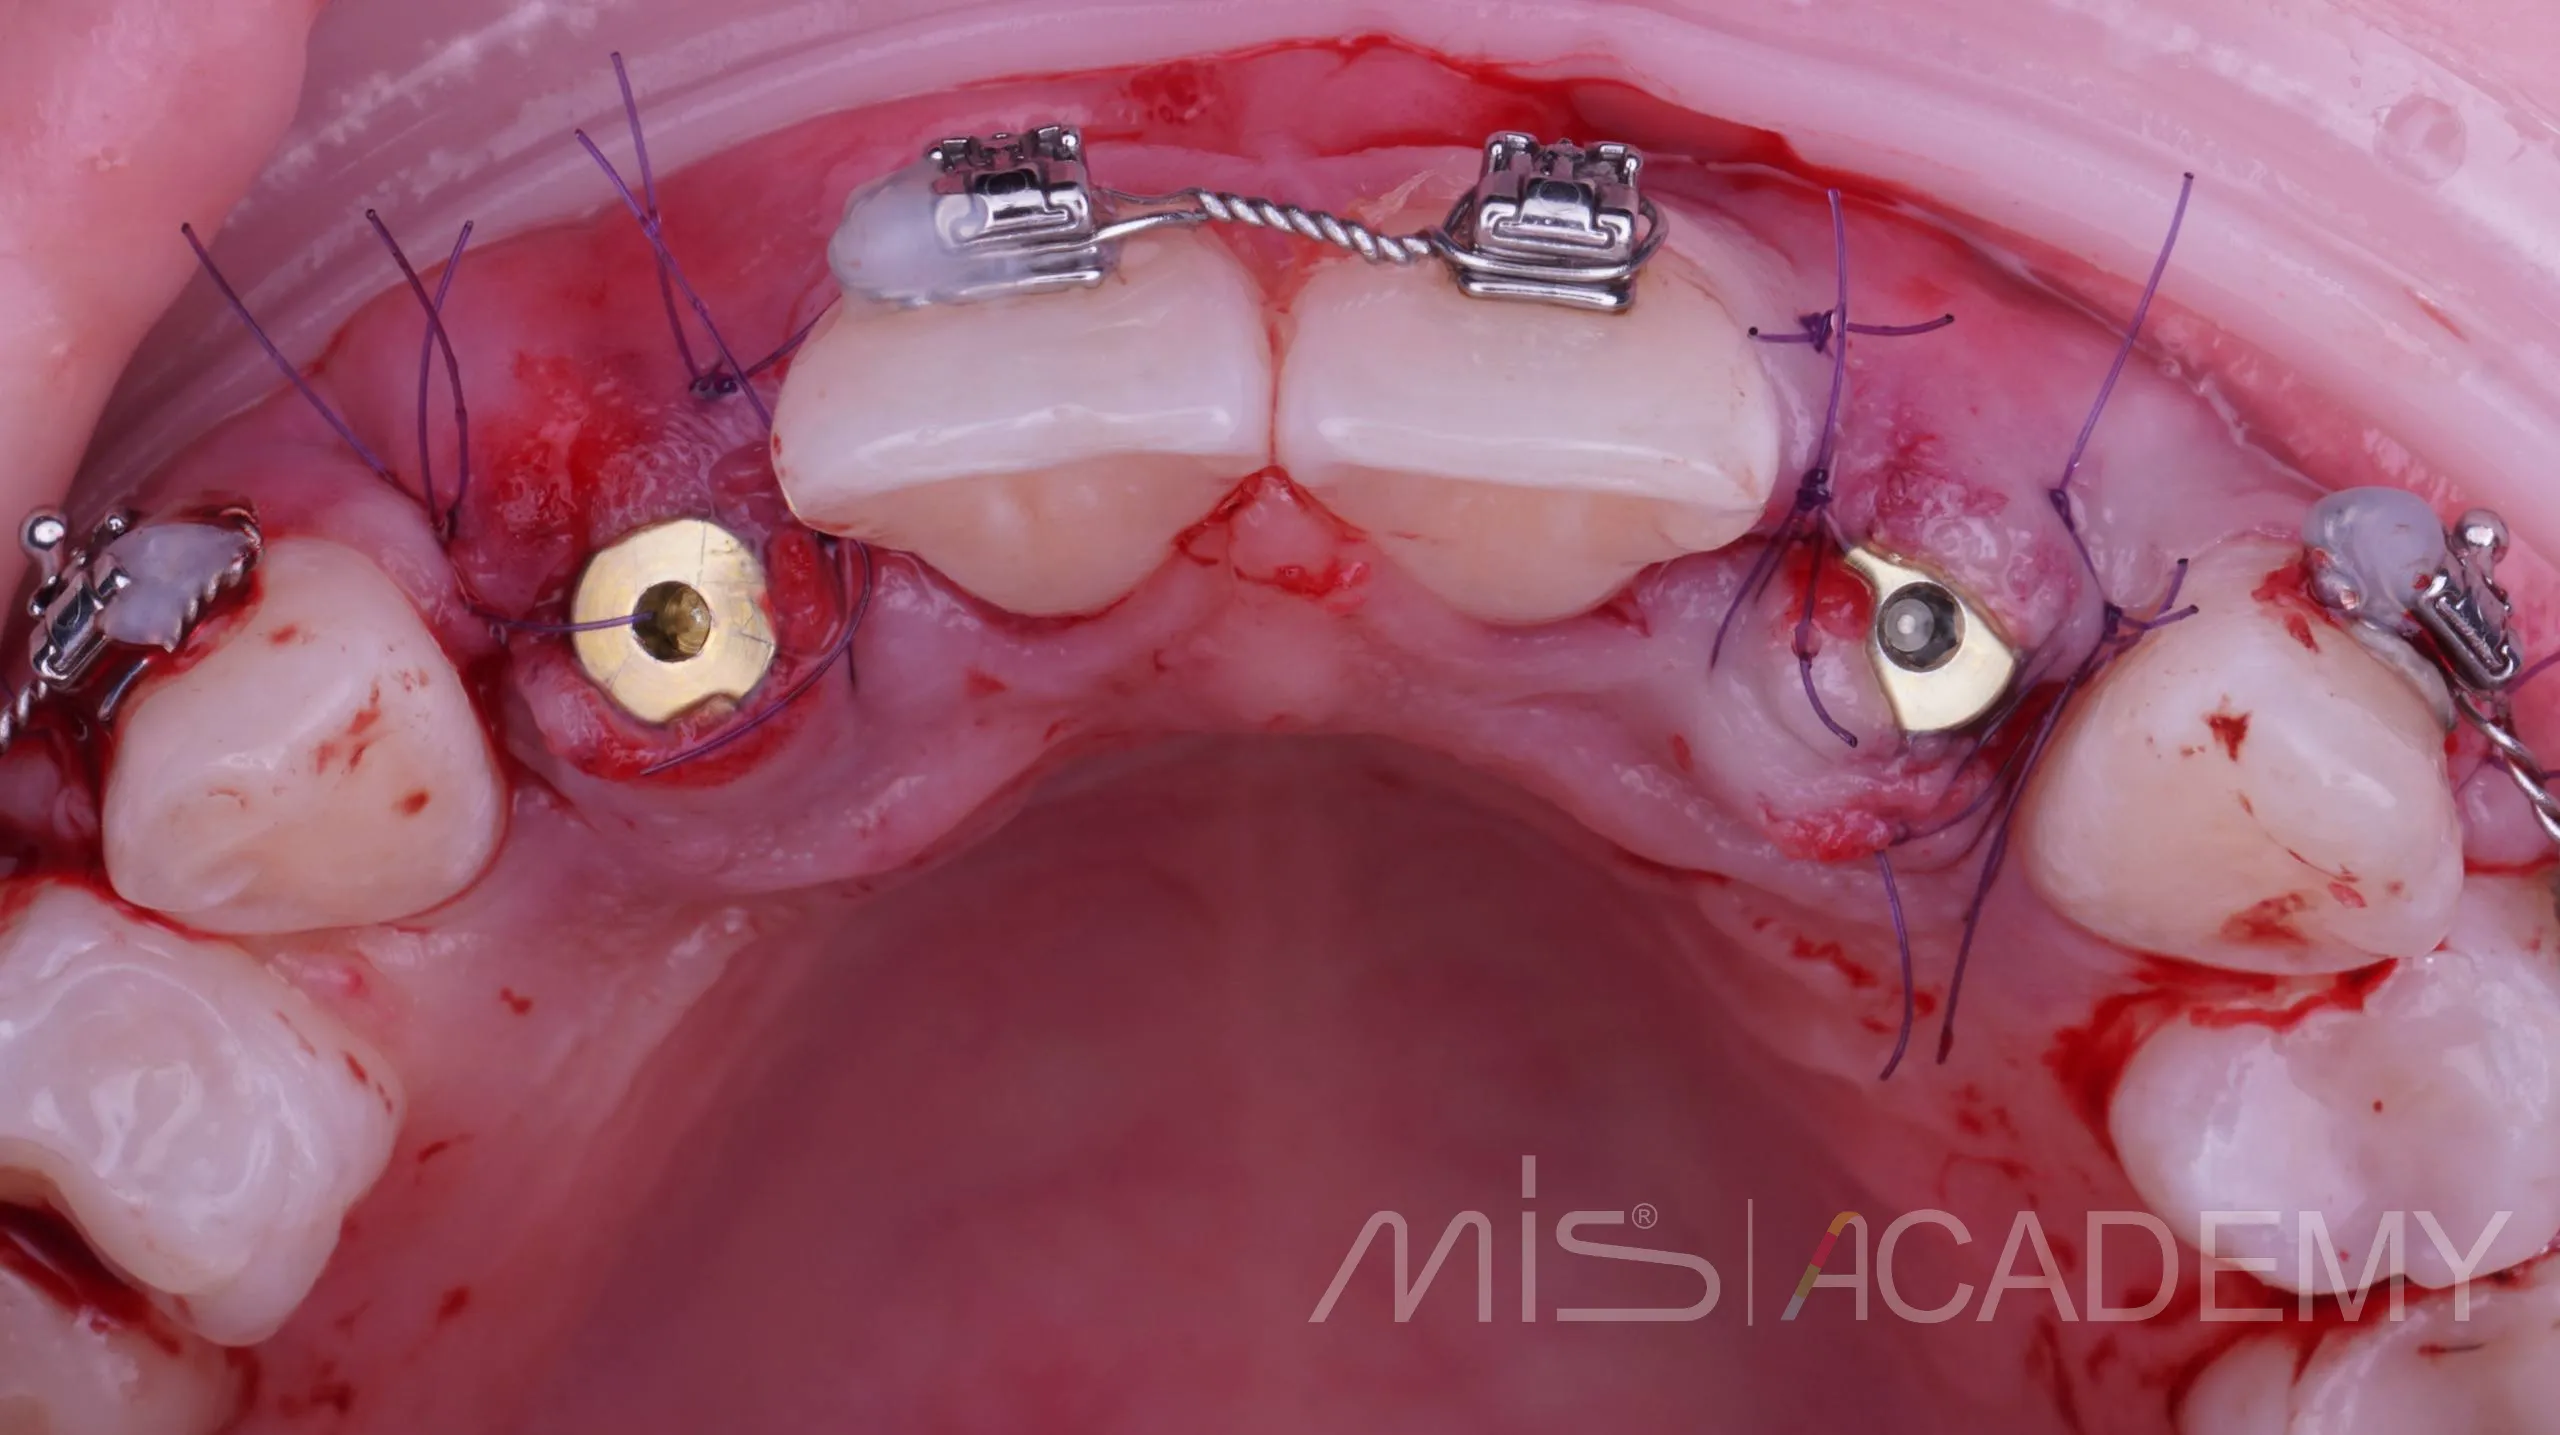

Небольшой рекол в 1 год после имплантации в область адентии двоек на верхней челюсти

— Имплантация MIS C1 узкая платформа.

— Connect абатменты.